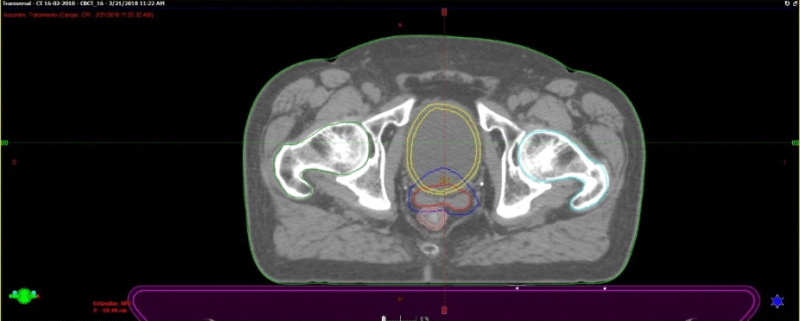

Se presentan figuras de un caso clínico de nuestro centro. Paciente de 57 años, APE: 6.5, Biopsia Gleason 7 (3+4) 2/6 sextantes. Etapificación (-), Rechaza cirugía.

Fig. 6. Tac con fiduciales y contornos. Dosimetría: 36.25Gy en 5 Sesiones, Días alternos. Los fiduciales son los puntos blancos dentro de la próstata semilla que se implantan previamente para tener un punto de referencia local confiables al realizar imágenes diaras previo al inicio de cada sesión.

Fig. 8. Paciente en tratamiento. Esta imagen corresponde el conbeamCT que se realiza en cada sesión de tratamiento y se superpone con el TAC previo de simulación que tiene los contornos. El contorno azul fue realizado previamente en el TAC de simulación. Así sabemos que la dosis llegará sólo sobre ese sector.